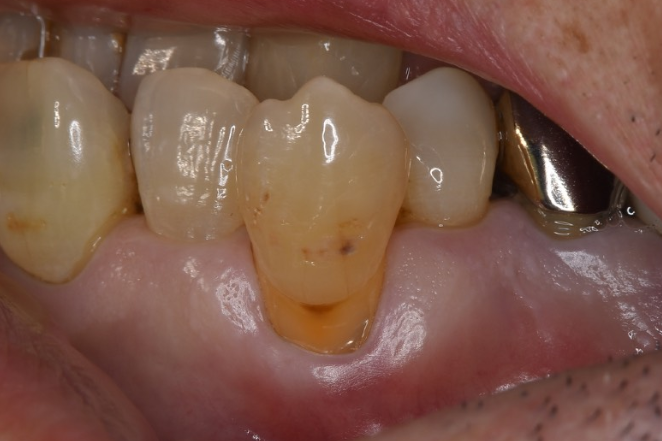

歯周組織再生療法の症例

症例1

| 項目 | 詳細 |

|---|---|

| 患者様データ | 56歳 女性 |

| 来院時の主訴 | 「左下の歯茎が下がっていると思っていたら今度は腫れてきた。前医では抜歯と言われた。」 |

| 医院の診断 | 左下第一大臼歯:慢性根尖性歯周炎と重度歯周病の併発、歯肉退縮 左下第二小臼歯・第二大臼歯・第三大臼歯:う蝕 |

| 通院期間 |

1年3か月 |

| 来院回数 | 15回 |

| 治療費 | 総額:650,000円(税抜) 歯周基本治療は保険適用診療 【内訳】 《保険適用診療》 歯周病検査・歯磨きや生活習慣指導・歯石取りクリーニング・第三大臼歯のCR充填 《自費診療》 第一大臼歯:精密根管治療 80,000円、歯根端切除術 100,000円、ファイバーポストコア 20,000円、歯周組織再生療法(歯肉結合組織移植併用) 170,000円、セラミック治療 120,000円 第二小臼歯・第二大臼歯:セラミック治療 80,000円×2 |

| リスクと副作用 | 定期的なメインテナンスが必要、破折リスク、正しい歯磨き習慣が必要不可欠 |

| ここがこだわりのポイント!☝ | 患者様の歯を抜きたくない、という願望に応える為、様々な技術を集結させています。患者様に頑張っていただいた結果、歯周病と合わせて歯茎下がりも改善することができ、治療後に気兼ねなく歯磨きが行えるようになりました。 |